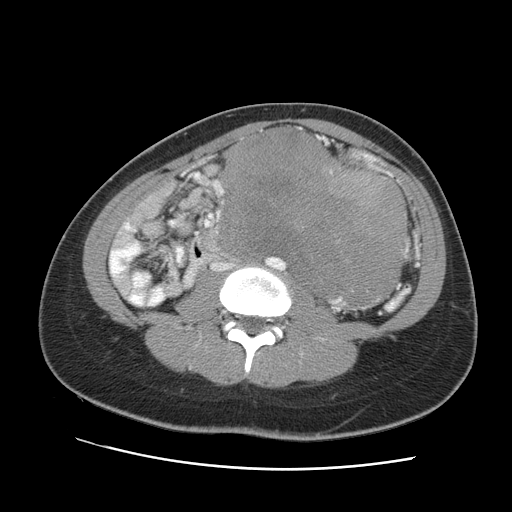

Evaluation of Intra-abdominal and Retroperitoneal Soft Tissue Masses

- Initial evaluation of intra-abdominal and retroperitoneal masses including laboratory studies, radiographic imaging, and genetic workup

- Discussion of when and how biopsies should be performed for intra-abdominal and retroperitoneal masses

- Discussion of management of complex sarcomas and when neoadjuvant chemotherapy or radiotherapy should be considered